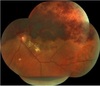

Quais são os achados fundoscópicos da OVCR?

Exsudatos Algodonosos

Hemorragias retinianas 360º

Edema de Disco

Tortuosidade vascular

Qual é o quadro fundoscópico apresentado?

Alterações localizar em um setor (TS em 63%)

Hemorragias retinianas

Exsudatos algodonosos

Tortuosidade vascula

Edema macular